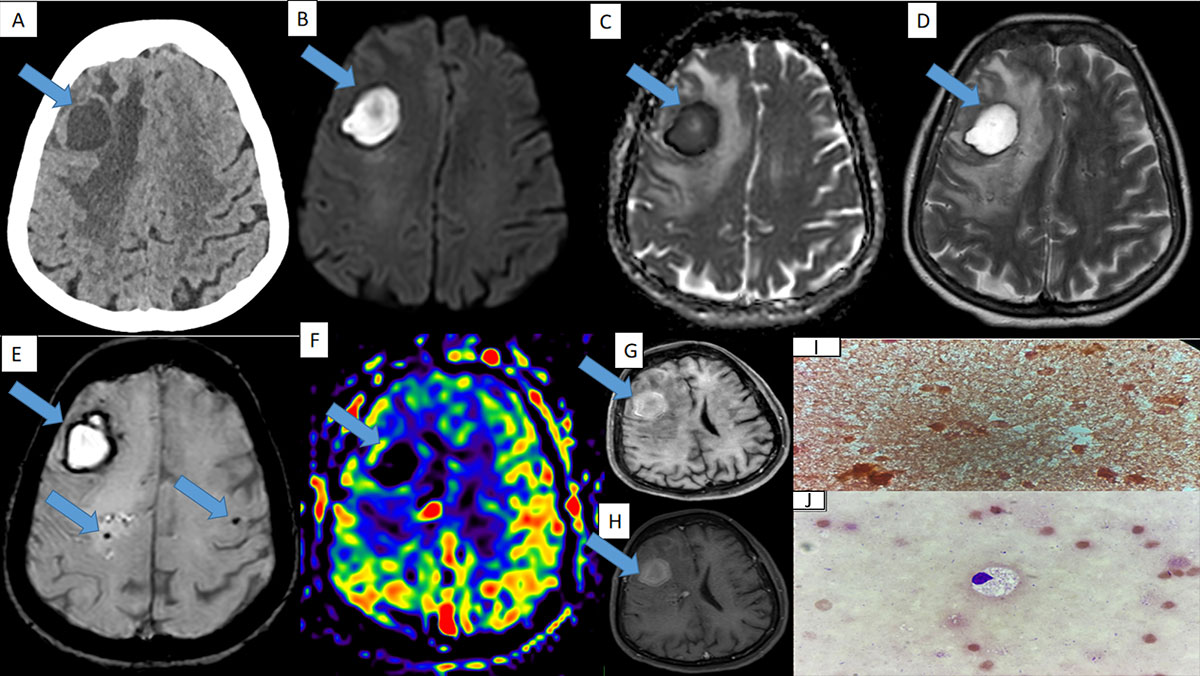

- A :Axial section of plain CT brain shows a well defined hypodense lesion in the right middle frontal gyrus with extensive perilesional edema in the right frontal lobe white matter.

- Band C : The lesion shows central diffusion restriction.

- D: Axial T2 sequence shows a well defined T2 hyperintense lesion seen in the right middle frontal gyrus with peripheral hypointense rim and extensive perilesional edema.

- E: Axial section of susceptibility weighted sequence shows peripheral blooming around the lesion with few microbleeds adjacent to the lesion.

- F: Axial section of arterial spin labelling sequence shows no perfusion at the centre and periphery.

- G and H: Axial section of pre-contrast T1 FS sequence and post-contrast T1 sequence showing peripheral enhancement on post contrast study.

- I: Gram stain – No pus cells. No organisms seen.

- J: Sediment smears from the fluid sample showed macrophages on a background of RBCs on Leishman stain. Pus culture report from specimen obtained from the showed no growth after 48hours of incubation.